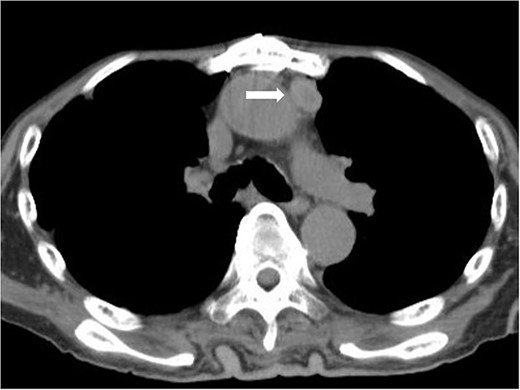

A 79-year-old man was referred to our hospital with an abnormal shadow on chest X-ray. He had a history of light smoking (3 pack-years) with no major past medical history. Physical examinations and laboratory tests, including tumor markers, were unremarkable. The chest CT revealed the presence of an anterior mediastinal mass, which had its longest diameter being 11 cm. The mass compressed adjacent great vessels and the heart posteriorly. On contrast-enhanced magnetic resonance imaging scan, the tumor presented as a well-demarcated, homogenously enhanced mass, and the direct invasion into surrounding structures was not apparent. Positron emission tomography (PET)-CT scan revealed a slight uptake of fluorodeoxyglucose (FDG) by the tumor (standardized uptake value [SUV] max = 3.32) and no signs of metastases (Fig. 1). Thymoma, thymic cancer, thymic neuroendocrine tumor or malignant lymphoma was suspected. However, ultrasound-guided percutaneous needle biopsy through the anterior chest wall revealed an undifferentiated sarcoma.

Contrast-enhanced chest CT scan (A) and FDG-PET scan (B) of the tumor (SUVmax = 3.32).